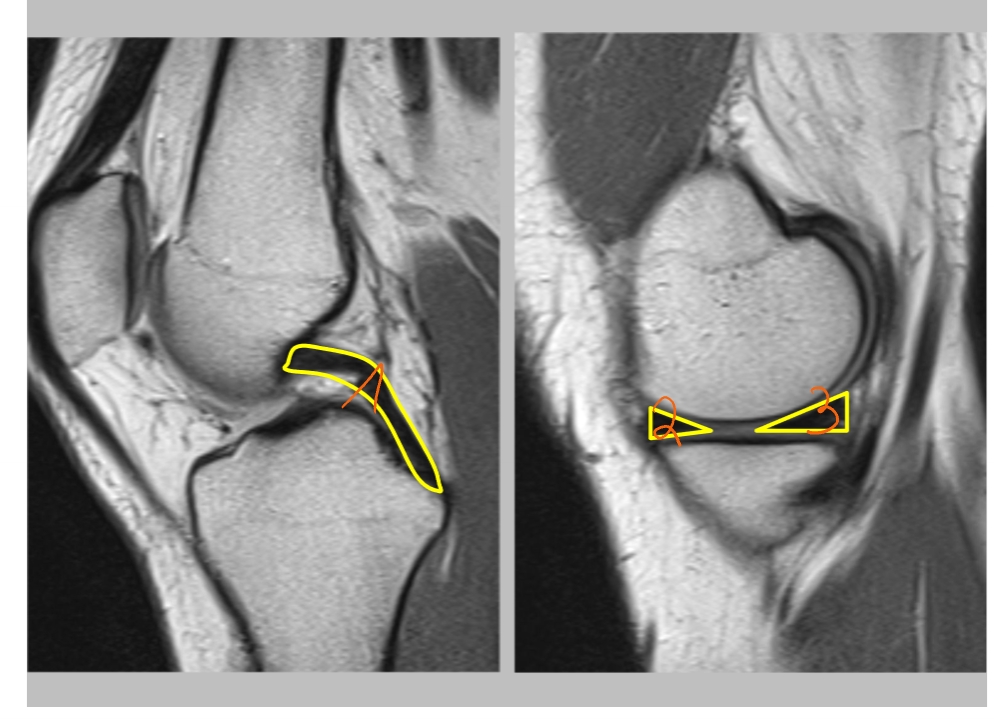

→ linker knie (MR): dwarse doorsnede

meniscus

anterieur

posterieur

voorste kruisband

achterste kruisband

meniscus (anterieur)

meniscus (posterieur)

tractus iliotibialis

mediaal collateraal ligament

lateraal collateraal ligament

→ linker knie (MR): coronale doorsnede